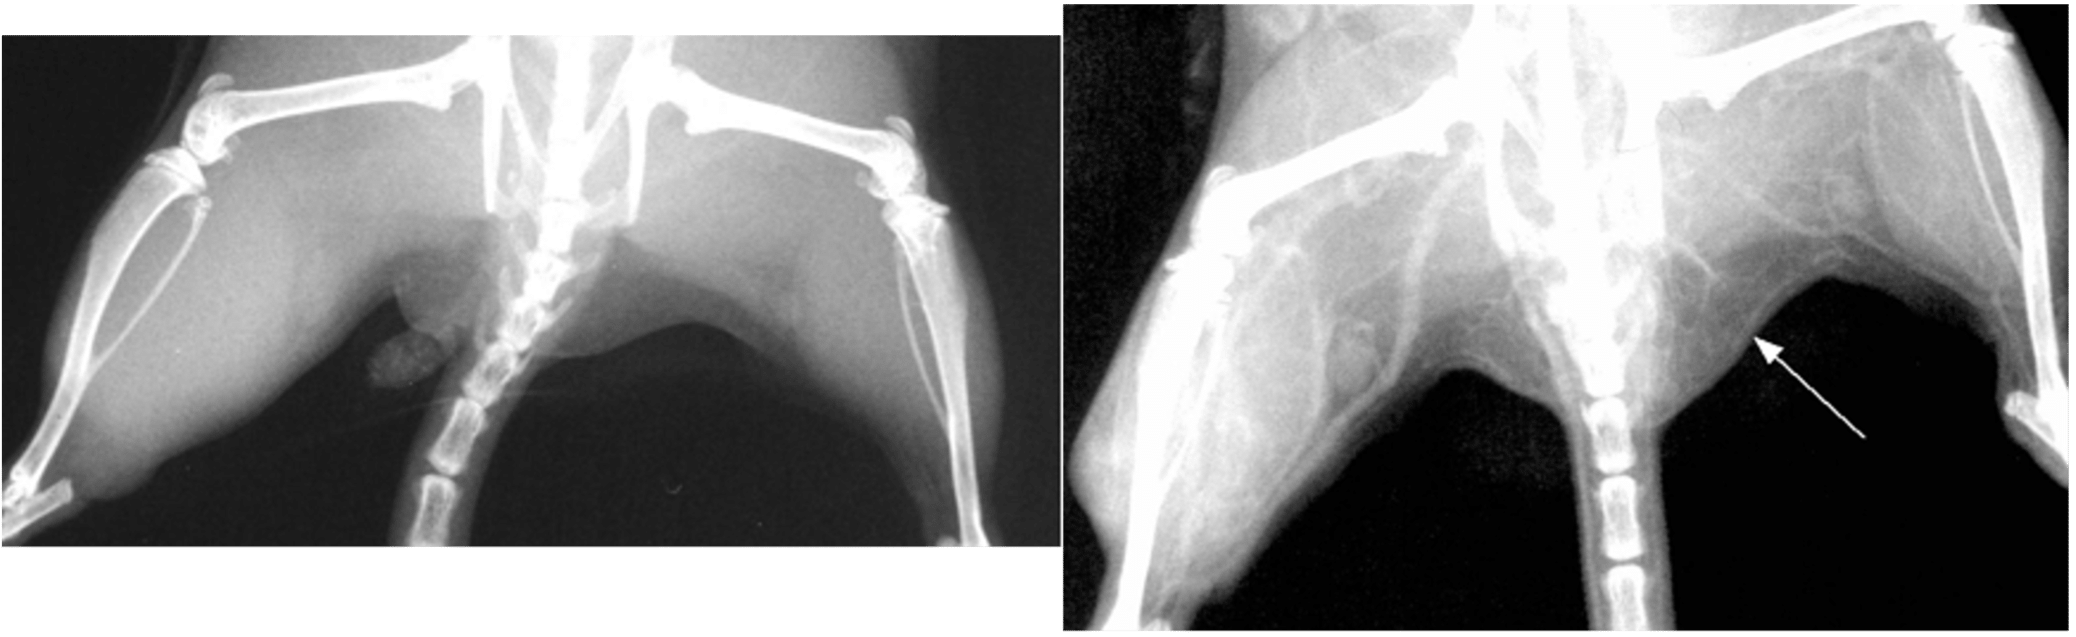

We developed biocompatible magnetic nanoparticles that selectively loaded tumors. When exposed to an AMF they heat up, enough to damage the tumor (Figs. 12, 13).

We found tumors could be heated to 50°C in as little as 5 sec. Although some mice could be “cured”, the equipment for treating humans is not available and the high level injected discolored skin for months and had poor clearance.

Read about it: “Intravenous Magnetic Nanoparticle Hyperthermia” https://doi.org/10.2147/ijn.s43770